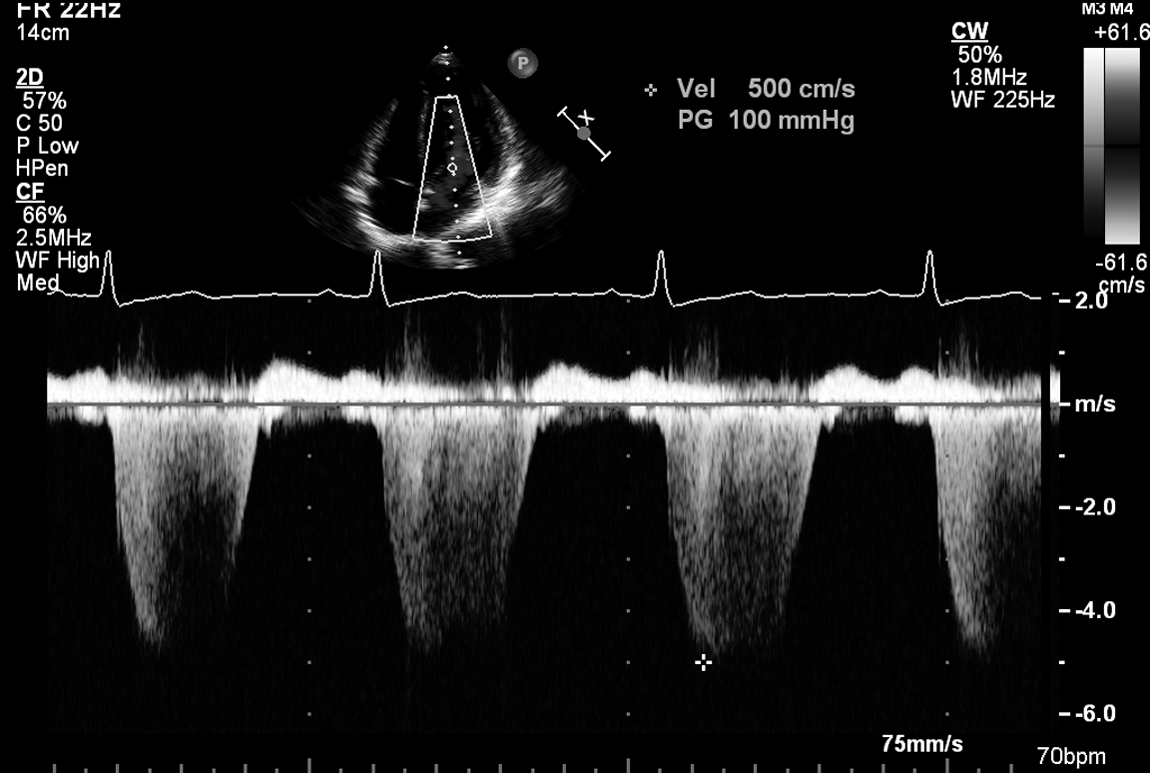

A 17-year-old girl who is normally fit and well presents with a few months of worsening ankle oedema and chest pain on exertion. There is no significant past medical history. Her echo is shown in Figure 18.1 and in Videos 18.1, 18.2, 18.3, 18.4, 18.5, 18.6 and 18.7.